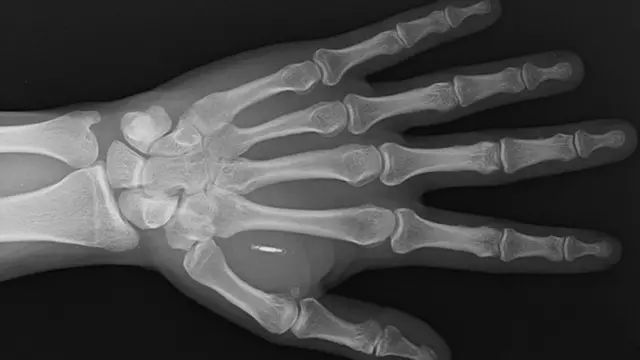

شريحة شركة واليتمور، يقل وزنها عن غرام واحد، ولا يتعدّى حجمها حبة الأرز، وتضم شريحة إلكترونية مدمجة، وهوائياً، داخل كبسولة من البوليمر الحيوي، وهي مادة طبيعية تشبه البلاستيك.

وأصبح باومان قادراً على الدفع بهذه الطريقة، لأنه زرع شريحة صغيرة، "مايكروشيب" تحت الجلد، عام 2019. ويضيف: "عملية حقن الشريحة تؤلم قليلاً، بمقدار قيام شخص ما بقرصك".